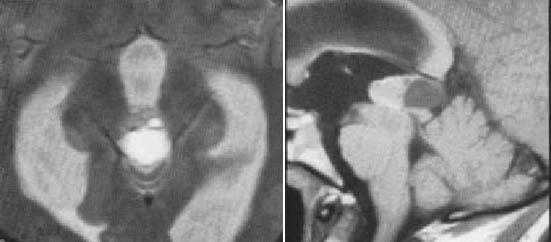

Пинеобластома. В режиме Т2 и Т1 выявляется опухоль задних отделов III желудочка мозга с развитием окклюзионной гидроцефалии. В строме опухоли небольшой участок подострого кровоизлияния. После в/в контрастирования опухоль интенсивно и достаточно гомогенно накапливает контрастирующее вещество.